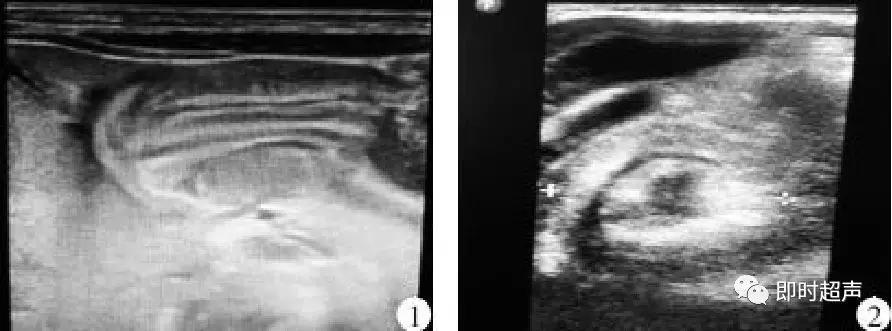

超声表现

球形、管状

与肠壁共肌层

重复的肠管与肠管相连

重复的肠管血供来源于肠系膜血管

肠重复畸形囊肿的声像图表现

- 无回声,极少数囊内有少量回声,罕见有分隔

- 大多数呈球形或管状,局部囊壁蠕动。

- 一般比肠系膜囊肿小。

- 囊肿壁声像结构与肠管壁相同,由内层回声增加的粘膜和粘膜下层与外围肌层的低回声组成,厚径约1~2mm

- 囊肿壁的肠壁样回声有助于与其他囊肿鉴别